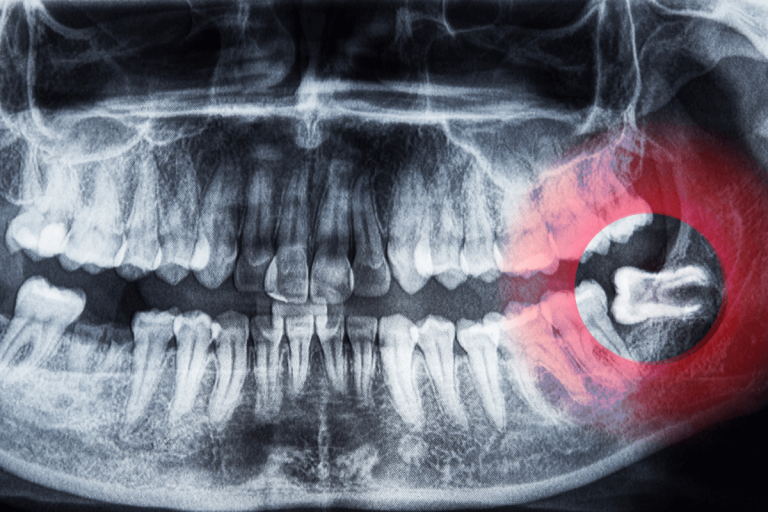

Рентгенови снимки по време на бременност – рентгеновите снимки по време на бременност се правят само при спешни случаи. Нивата на радиация трябва да са минимални, затова трябва да се вземат предпазни мерки като оловни щитове и други.

Специализирана дентална клиника Бушкалова разполага с опитни лекари по дентална медицина и орални хирурзи, в чиито ръце може да се чувствате спокойни, когато се наложи вадене на мъдрец. В клиниката разполагаме и с напълно оборудвана операционна, в която се извършват процедури под седация и обща анестезия, така че ще се погрижим качествено и за най-трудните и заплетени случаи. Освен това разполагаме с ултра модерен дентален компютърен томограф и рентгенов кугел. С помощта на прецизната образна диагностика оралния хирург или зъболекаря взима най-точното и безопасно за пациента решение как да протече денталната процедура по екстракция на зъба. Запазете своя час за преглед.